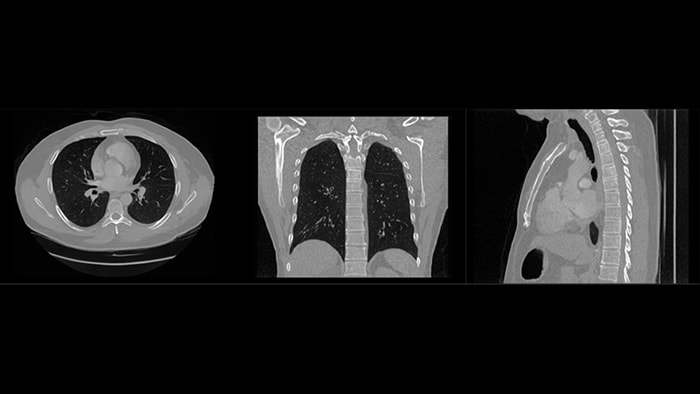

Philips’ collaboration with medical centers in Zurich and Utrecht is transforming care in cardiology and oncology. Through technological advancements in imaging and image guidance, we are enabling surgeons to perform minimally invasive procedures in place of open surgery and in some cases, any surgery at all.

Philips receives FDA 510(k) clearance for its Rembra platform, expanding access to faster, more precise CT imaging across frontline care and cancer treatment planning

Click to read morePhilips receives FDA 510(k) clearance for Verida, the world’s first AI-powered detector-based spectral CT*, advancing diagnostic precision across clinical applications